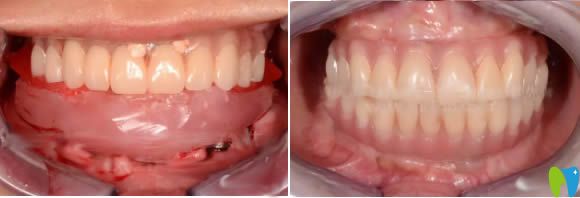

差不多多半個小時,種植系統(tǒng)已經(jīng)就植入好了,如下圖↓↓↓

經(jīng)歷種牙過程后,我覺得也沒有那么恐怖,就是打麻藥的時候疼一些,整個過程沒有太大的疼痛感呢。

下圖是我剛做完上頜種植牙和下頜牙的即刻效果: